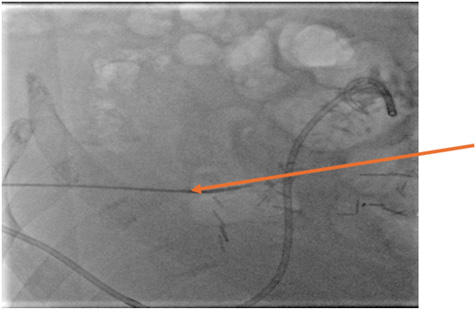

Six weeks postoperatively, the patient was able to transfer to an acute rehabilitation facility. There, he began to tolerate PO intake and after one month in rehab, the GJ tube was able to be removed. The pigtail drain remained in place with persisting, cloudy fluid drainage. One month later, output from the pigtail drain evolved, becoming succus and consistent with enteric content. Output ranged between 200cc and 300cc daily. The patient returned to IR multiple times over several months on an outpatient basis, undergoing abscessograms, drain reposition, and drain upsizing. Abscessogram ultimately demonstrated the positioning of the catheter with the pigtail terminating within the lumen of the small bowel, consistent with an iatrogenic enterocutaneous fistula (Image 3).